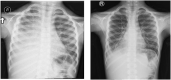

Case presentation: A 4-years-old male subject presented with a recurrent chylothorax and bilateral lower limb edema that started at age of 6 months. Lymphoscintigraphy showed lymphangiectasia with chylothorax. The whole exome sequence consisted of Pathogenic variants in PIEZO1 gene associated with lymphatic malformation type 6 (LMPHM6).